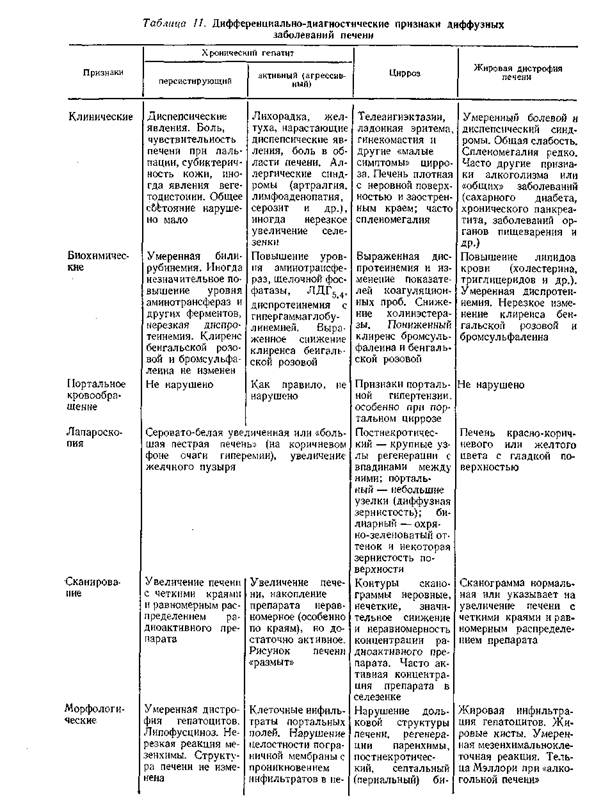

В табл. 11 приведены дифференциально-диагностические признаки диффузных заболеваний печени.